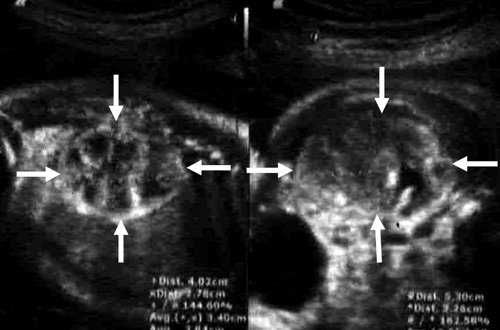

Левая почка была увеличена до 31×19×25 мм, преимущественно за счет анэхогенного образования с однородным содержимым до 16 мм в диаметре. Образование исходило из верхнего полюса почки и располагалось под ее капсулой. Сама почка была смещена книзу. При этом лоханка была незначительно расширена - до 4 мм, в то время как чашечки расширены не были. Левый мочеточник не визуализировался (рис. 3).

Рис. 3. Кистозное образование у верхнего полюса левой почки плода.

Область правой почки занимало округлое тонкостенное анэхогенное образование до 36 мм в диаметре. Правая почка была уменьшена в размерах до 17×9×20 мм, смещена и располагалась, распластываясь в виде полумесяца по задней поверхности образования (рис. 4). Правый мочеточник не визуализировался. Паренхима обеих почек была повышенной эхогенности, кортикомедуллярная дифференцировка почечных слоев нечеткая.

Рис. 4. Образование возле правой почки и расширенный мочевой пузырь плода.